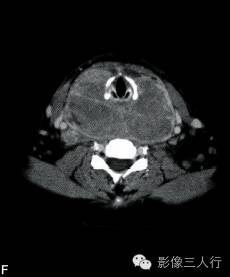

A~C.CT平扫横断面;D~F. CT增强横断面;G. HE×40

【影像学表现】

双侧甲状腺、颌下腺及咽淋巴环见多发结节融合状软组织影,边界不清,可见包膜,病灶密度欠均匀,内可见线样分隔,未见明显坏死及钙化,双颈各区可见大小不等的淋巴结,边界欠清,密度较均匀(图A~C)。增强横断面(图D~F)扫描双侧甲状腺、颌下腺及咽淋巴环病灶包膜及分隔可见明显强化,双颈淋巴结可见较明显强化。